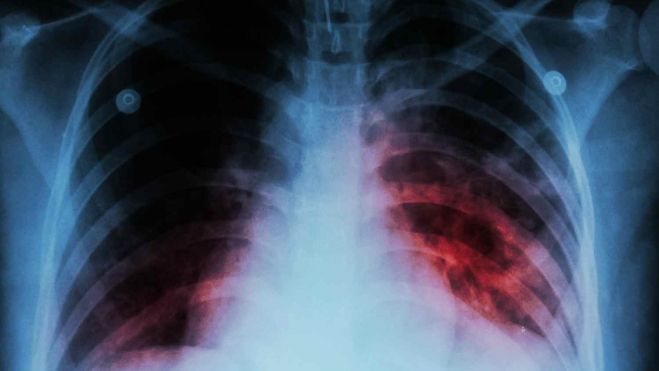

Con la prueba de tuberculina (o Mantoux), lo que se comprueba es si una persona tiene o no Mycobacterium tuberculosis en su organismo. Si esta sale positiva, puede ser que tenga la enfermedad activa y la pueda contagiar o simplemente que tiene el germen en el cuerpo de manera latente (por contacto con alguien enfermo o simplemente por vacunación en la infancia con la BCG). Es decir, se necesitan más pruebas, aparte del Mantoux, para determinar si puede transmitir la enfermedad: rx de tórax, cultivo de esputo o la prueba de IGRA (ensayo de liberación de interferón gamma en sangre). Las pruebas de imagen han sido informadas por un neumólogo del CAULE. En este caso, de 34 contactos estrechos que se estudiaron ninguno tiene tuberculosis.